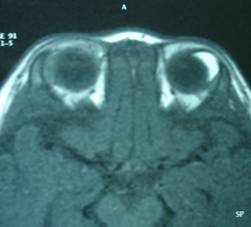

Dermoid: is a benign tumor of the conjunctiva presenting as a solid mass in the conjunctiva or near the cornea. It may be associated with other diseases. They are generally small but large ones can affect vision in which case they require surgical treatment.

| CT scan in the right eye with appearance of a white crescent corresponding to the lesion | |